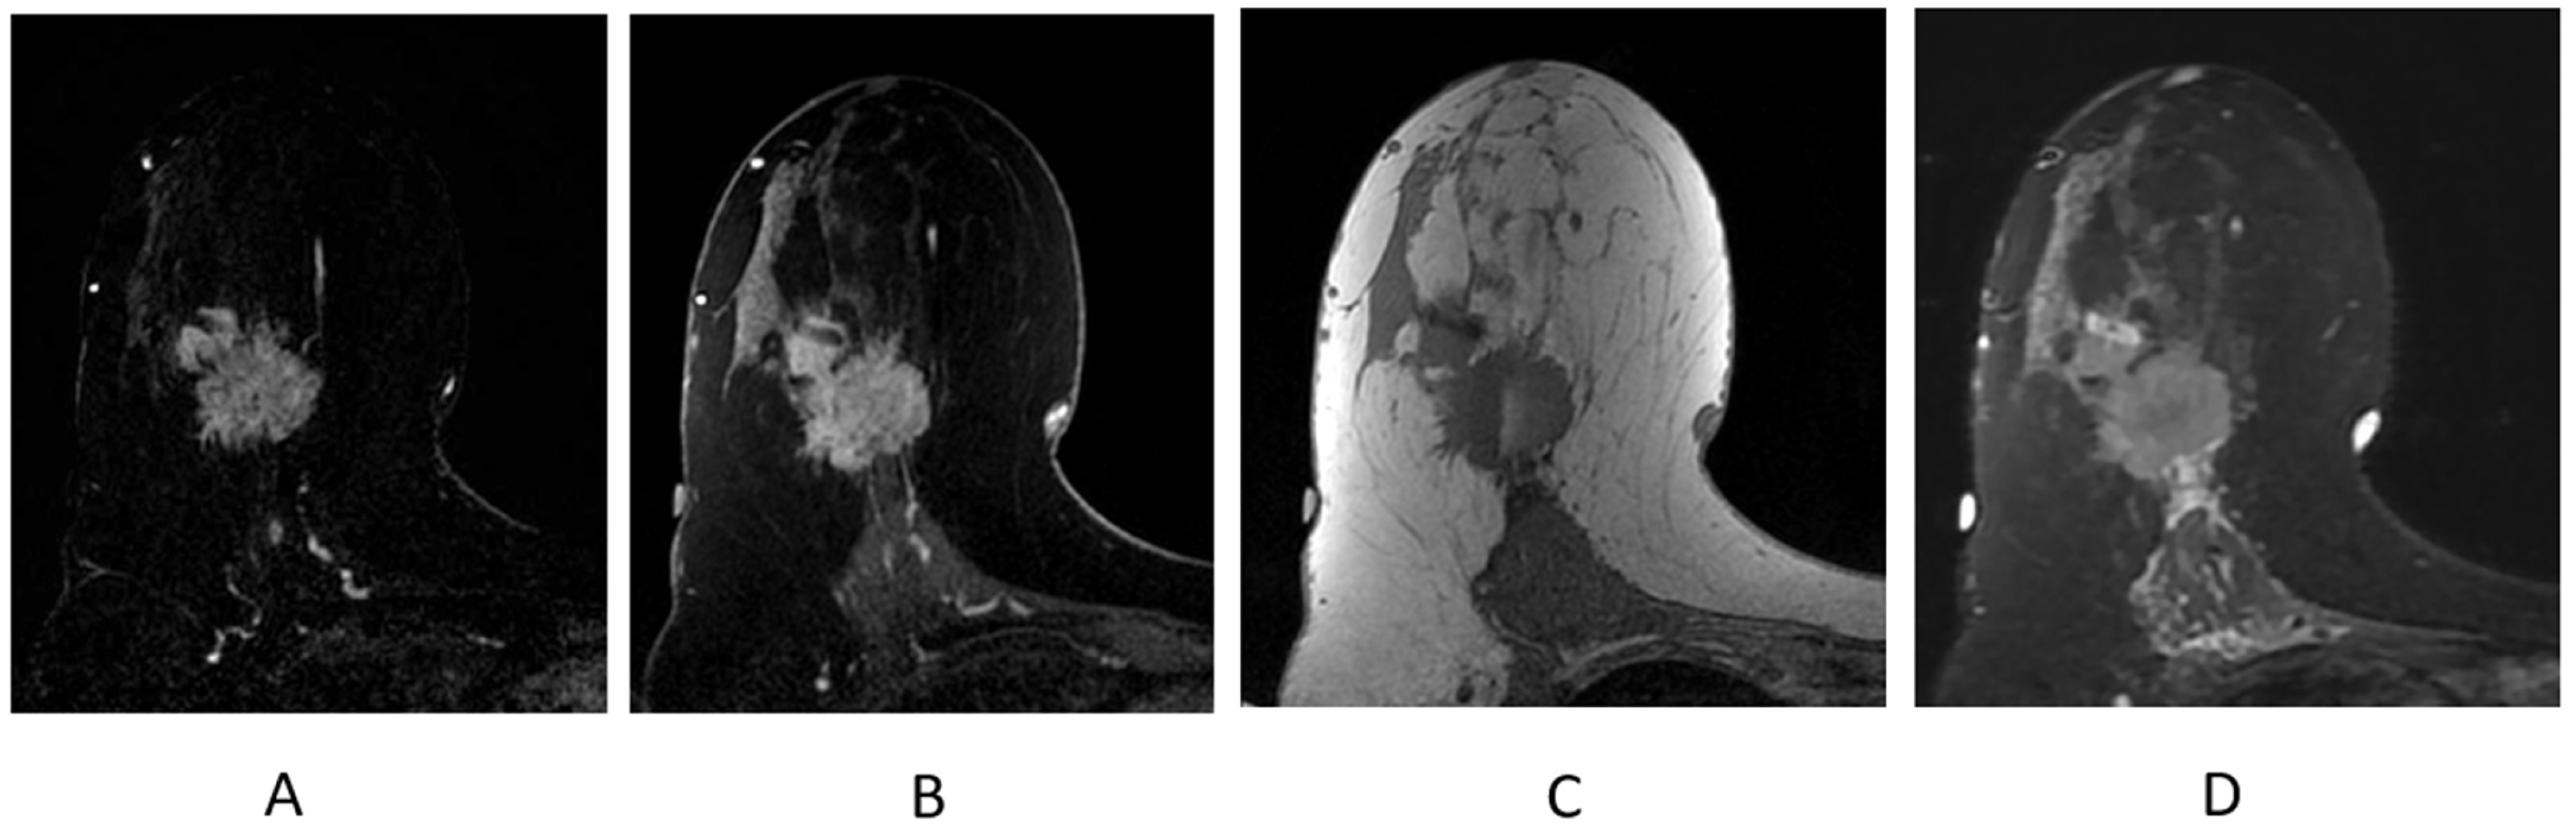

The majority of enhancing breast cancers will be conspicuous on the first post-contrast T1-weighted sequence, particularly on the post-processed subtraction image (Figure 9A). The “source” images—the post-contrast T1-weighted fat-suppressed sequence—will demonstrate the enhancing cancer and provide information on the parenchymal contour and nearby anatomic landmarks (Figure 9B); these are the best sequences in the evaluation and contouring of a breast malignancy.

Figure 9.

Invasive ductal carcinoma presenting as an irregular mass on breast MRI. (A) Axial post-contrast subtraction, first time point; (B) axial post-contrast T1-weighted fat-suppressed sequence; (C) axial T1-weighted non-fat-suppressed sequence; (D) axial STIR sequence.